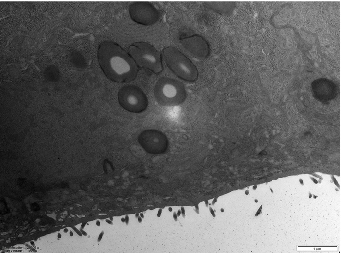

Microvilli are critical ultrastructural components of the intestinal epithelium; they can maintain epithelial barrier integrity and regulate paracellular permeability [28]. Transmission electron microscopy revealed distinct morphological differences: the control (Ctrl) monolayers exhibited densely packed microvilli with organized brush borders, whereas treated LPS displayed severe loss of microvilli and widened intercellular spaces accompanied with a disordered manner (Figure 4). Postbiotic intervention restored the density and structural organization of microvilli across all groups, with Pa JY062 demonstrating the most significant microvillus morphology.

1. Figure 4. The effect of postbiotics on the ultrastructure in LPS-induced intestinal epithelial barrier dysfunction (magnification: ×20,000; n = 3).

Figure 4. The effect of postbiotics on the ultrastructure in LPS-induced intestinal epithelial barrier dysfunction (magnification: ×20,000; n = 3).